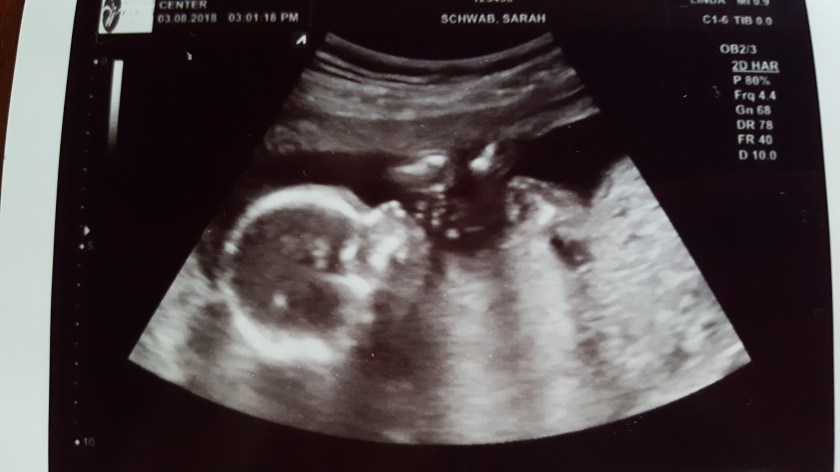

And….shortly after that we’ll add baby number 10! Again, a nice even number π

Abundantly blessed by our awesome Creator, the One who created this new being to be a part of this family and this world at this time? There’s no doubt.